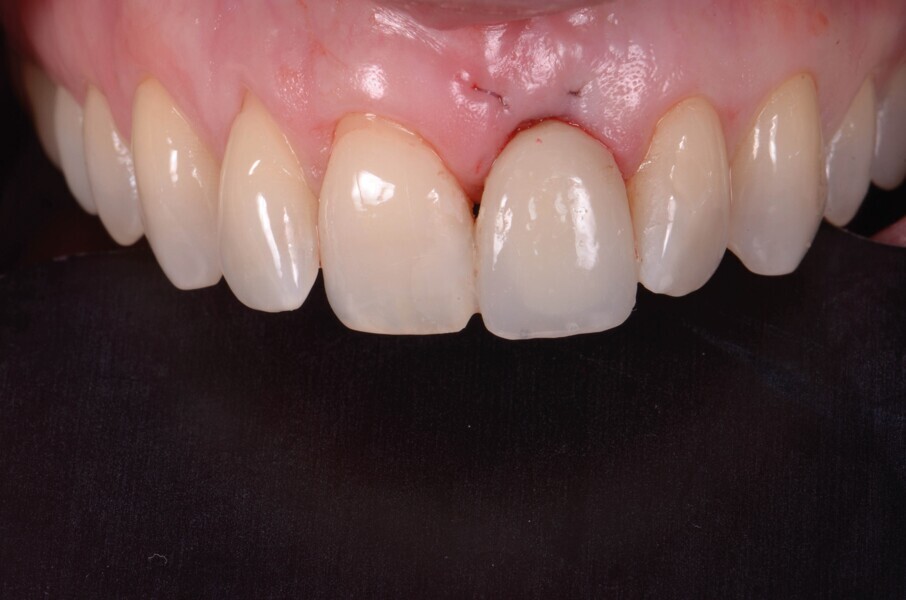

Un implant (Aadva Regular, GC Tech), avec une connexion conique interne associée au concept du platform switching, est mis en place (Figs. 11–12). La dent provisoire est ensuite collée à nouveau aux dents adjacentes

(Fig. 13a). Au bout de quatre mois, l’ostéointégration de l’implant est obtenue et cette fois encore, les tissus mous sont bien intégrés (Fig. 13b). La phase prothétique peut alors débuter.

Fig. 13a : Immédiatement après la pose de l’implant.

Fig. 13b : Quatre mois (b) après la pose de l’implant.